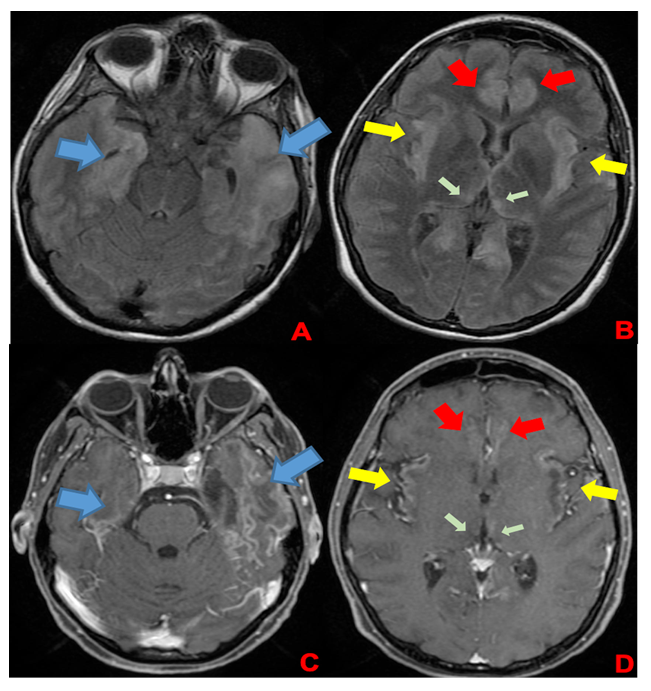

A 35-week pregnant woman was diagnosed with dengue fever. Within three days, she developed confusion and seizures, requiring emergency caesarean section and mechanical ventilation. Brain computed tomography revealed a hypodense lesion in the left temporal lobe with mass effect compatible with limbic encephalitis (Figure 1). Cerebrospinal fluid (CSF) analysis showed 40 cells/mm³ and 80 mg/dL of protein. Empirical intravenous acyclovir (10 mg/kg every 8 h) was initiated because of the presumptive diagnosis of herpetic encephalitis. After 9 d, she was extubated but remained cognitively impaired and was discharged 11 d later with partial neurological recovery. Two days later, she was admitted to a tertiary referral hospital with fever and generalized weakness. Brain magnetic resonance imaging (MRI) demonstrated the involvement of limbic structures, hyperintensities in the cortical and subcortical brain parenchyma with subtle mass effects, cortical enhancement in these regions, and findings consistent with volume loss in the left mesial temporal lobe and insular cortex, likely resulting from previous encephalitis (Figure 2). MRI revealed demyelinating lesions in the cervical and thoracic spinal cord (Figure 3). CSF analysis showed 57 cells/mm³, more than 300 mg/dL protein, and glucose of 42 mg/dL. Molecular tests, including those for dengue and herpesviruses, as well as metagenomic sequencing of CSF, were negative. A comprehensive panel for autoimmune encephalitis in both the blood and CSF also yielded negative results. She received pulse methylprednisolone for 5 d, followed by intravenous immunoglobulin for 5 d, with slight cognitive improvement.

FIGURE 2: First brain MRI of the patient. In the superior row (A and B), axial FLAIR images; in the inferior row (C and D), axial T1 post-contrast images. Findings demonstrate encephalitis with involvement of limbic structures such as the temporal lobes (blue arrows), insula (yellow arrows), cingulate gyrus (red arrows), and medial portions of the thalami (green arrows). FLAIR images (A and B) show hyperintensities in cortical and subcortical brain parenchyma with a subtle mass effect, while post-gadolinium images demonstrate cortical enhancement in these regions and findings consistent with volume loss in the left mesial temporal lobe and insular cortex, likely resulting from previous encephalitis